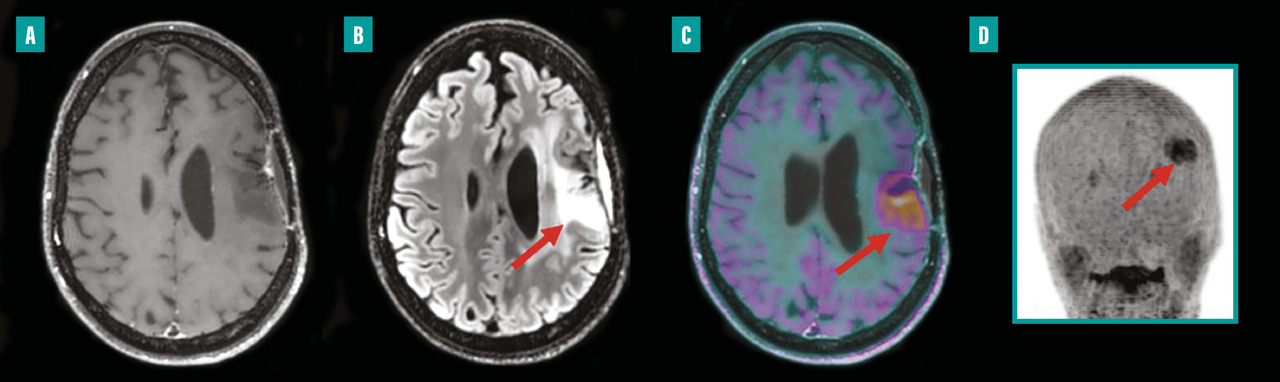

Depuis environ une décennie, des systèmes hybrides alliant TEP et imagerie par résonance magnétique (IRM) sont disponibles en milieu clinique. La TEP-IRM présente l’avantage d’exposer les patients à moins de radiations que la TEP, ce qui est particulièrement bénéfique pour les enfants ou les personnes nécessitant des examens répétés dans le cadre de leur traitement. L’intégration de l’IRM améliore considérablement l’analyse des tissus mous et assure une correspondance spatiale parfaite avec les anomalies fonctionnelles détectées par la TEP. Grâce à sa haute résolution, la TEP-IRM permet d’examiner avec précision les petites structures et de détecter les changements subtils dans les images au cours du traitement. En oncologie, la TEP-IRM est principalement utilisée pour les patients atteints de cancers pelviens (gynécologiques et de la prostate) ainsi que pour les cancers ORL et en neuro-oncologie (fig. 1).9